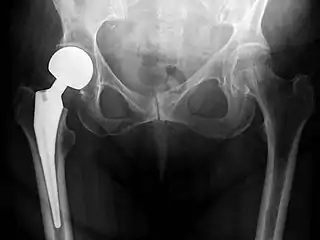

Hip replacement is a surgical procedure in which the hip joint is replaced by a prosthetic implant, that is, a hip prosthesis. Hip replacement surgery can be performed as a total replacement or a hemi/semi(half) replacement. Such joint replacement orthopaedic surgery is generally conducted to relieve arthritis pain or in some hip fractures. A total hip replacement (total hip arthroplasty or THA) consists of replacing both the acetabulum and the femoral head while hemiarthroplasty generally only replaces the femoral head. Hip replacement is one of the most common orthopaedic operations, though patient satisfaction varies widely. Approximately 58% of total hip replacements are estimated to last 25 years.[1] The average cost of a total hip replacement in 2012 was $40,364 in the United States, and about $7,700 to $12,000 in most European countries.[2]

Post-operative projectional radiography is routinely performed to ensure proper configuration of hip prostheses.